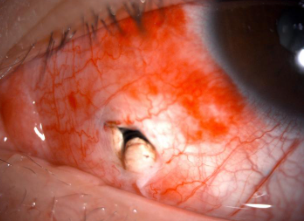

检查发现,王同学的晶体全白混浊,眼球穿通、巩膜裂伤,玻璃体崁顿在巩膜裂口处,随时有感染眼内炎症的风险。

巩膜短“Y”型全层裂伤